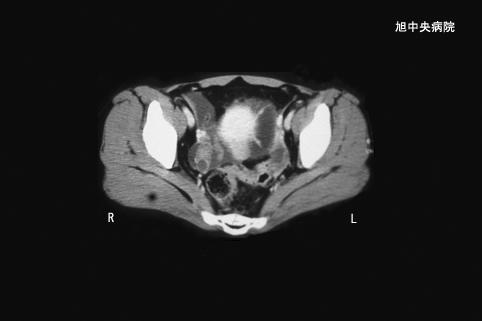

症例提示(所在地,施設名等): 千葉県・ 旭中央病院

症例登録日 2002/06/27

画像ID:3498

疾患(病理主体)の分類腫瘍様病変/子宮内膜症

部位(臓器別)小腸/回腸

検査方法CT

病変の最大径(ミリ)35〜40